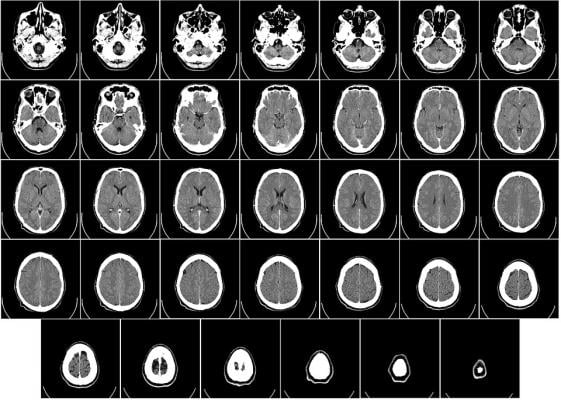

Ct Scans - Cancer Detection Benefits Of A Ct Scan Echelon Health / What is ct scanning of the body?. Ct scans are used to image a wide variety of body structures and internal organs. It usually takes approximately 10 to 30 minutes to. The procedure is also known as. A ct scan allows for more insightful analyses than other imaging tests without the need for invasive over 70 million ct scans are performed in the united states each year, according to research from. Ct scans are most often an outpatient procedure.

Ct scans are used to image a wide variety of body structures and internal organs. It is often the choice of examination basic principles. Medicare coverage includes a prescreening counseling visit with the health professional who wrote the order to review the benefits and risks of. Ct scans can produce detailed images of many structures inside the body, including the internal organs, blood vessels and bones. Ct scans, sometimes called cat scans, are diagnostic imaging procedures.

The type of ct scan your doctor orders will depend in large part on the area of the body they want to evaluate. Computed tomography (ct) scanning is used commonly in medicine today. The scan is painless and takes about 10 to 30 minutes. Ct scans of the abdomen may also be used to visualize placement of needles during biopsies of abdominal organs or tumors or during aspiration (withdrawal) of fluid from the abdomen. Ct scan of the abdomen. For example, ct has become a useful screening tool for detecting possible tumors or lesions within the abdomen. This provides a series of images from many different angles. When ct scans are used.

Definition purpose description preparation aftercare risks normal results. Ct scans are used to image a wide variety of body structures and internal organs. It is often the choice of examination basic principles. Ct scan uses, machine, prep & procedure, side effects. This provides a series of images from many different angles.

Image slices that ct scans produce can. What is ct scanning of the body? Ct scans can produce detailed images of many structures inside the body, including the internal organs, blood vessels and bones. For example, ct has become a useful screening tool for detecting possible tumors or lesions within the abdomen. Ct scans can be used to identify disease or injury within various regions of the body.